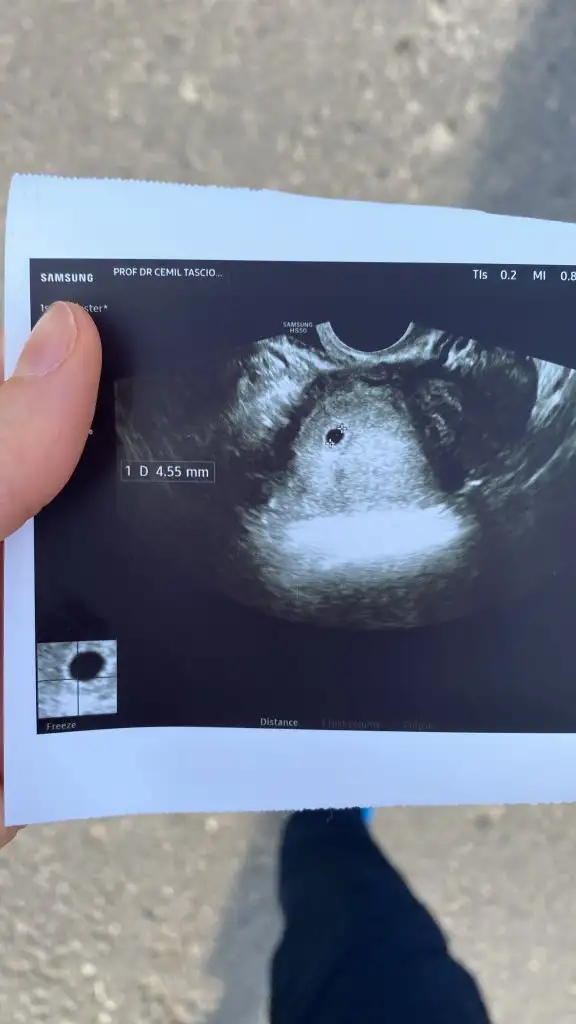

Kızlar bende anlık keseyi görmüş bulunuyorum🤲❤️ 5+2 olmam lazım doktor 4-5 haftalık gibi dedi

Eklentiler

• D4798BD7-094F-4905-8DDD-9EB70CB844A0.webp

D4798BD7-094F-4905-8DDD-9EB70CB844A0.webp

20,3 KB · Görüntüleme: 94